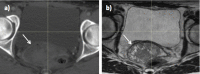

CT-based radiotherapy workflow is limited by poor soft tissue definition in the pelvis and reliance on rigid registration methods. Current image-guided radiotherapy and adaptive radiotherapy models therefore have limited ability to improve clinical outcomes. The advent of MRI-guided radiotherapy solutions provides the opportunity to overcome these limitations with the potential to deliver online real-time MRI-based plan adaptation on a daily basis, a true "plan of the day." This review describes the application of MRI guided radiotherapy in two pelvic tumour sites likely to benefit from this approach.